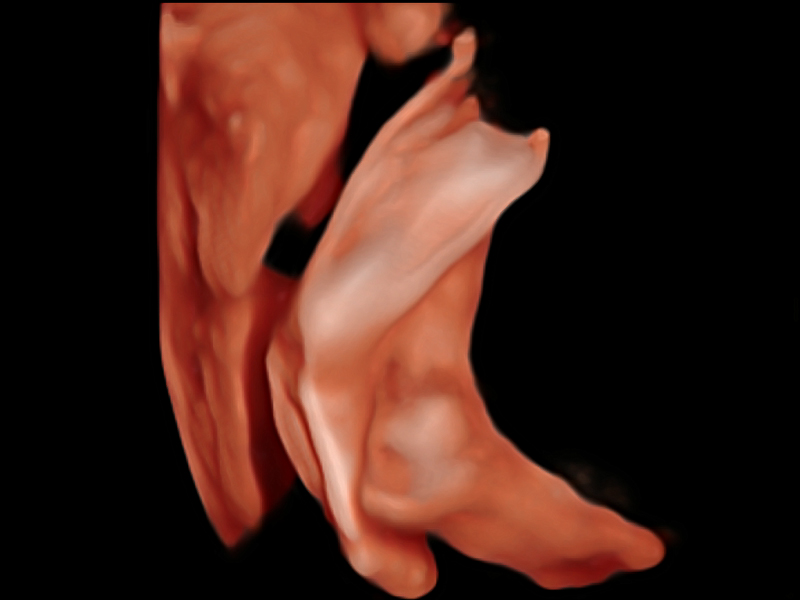

S-Fetus基于大數(shù)據(jù)深度學(xué)習(xí)算法,能夠幫助您在產(chǎn)前篩查過程中智能識別胎兒標(biāo)準(zhǔn)切面、自動測量并錄入報告。一個按鍵,即可智能、精準(zhǔn)、高效地獲取胎兒生理指標(biāo),極大簡化您的產(chǎn)科檢查操作。

可快速對產(chǎn)科掃查切面完成胎兒生理學(xué)參數(shù)的自動測量,減少操作者按鍵次數(shù),大幅提升檢查效率。